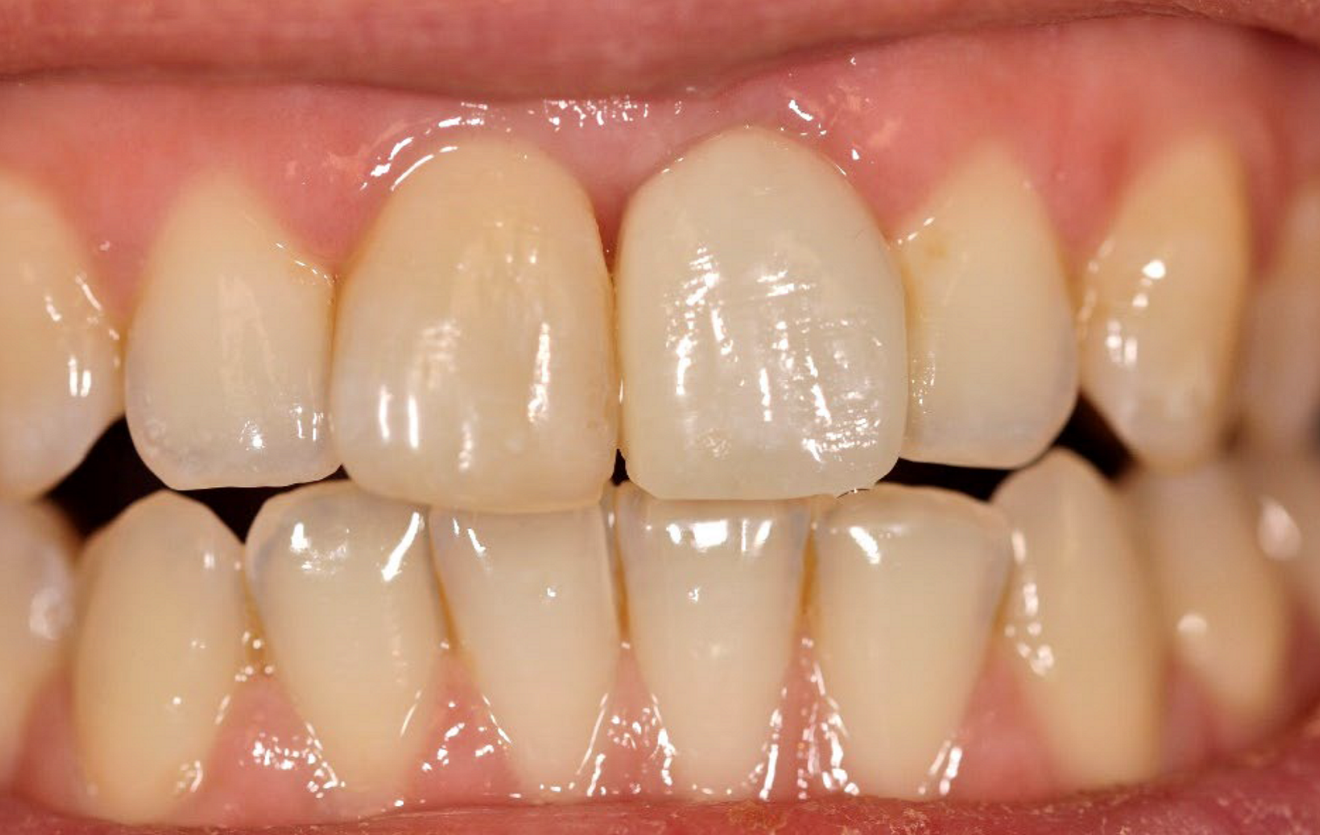

Radiograph (g) ...

.. and clinical view at the seven-year follow-up (h).